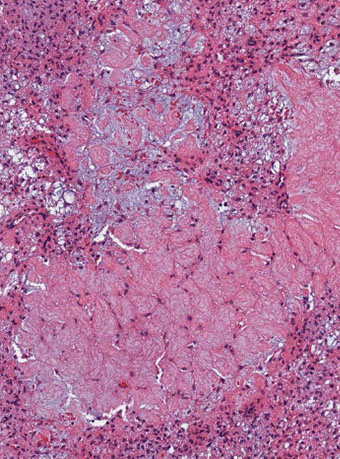

Micro: Islands of cartilage permeating viable lamellar bone; bone made by enchondral ossification

- classified into 3 grades based on cellularity, atypia and pleomorphism

-- most are grades 1 (lobulated; resembles chondroma) or 2 (not lobulated and made of spindle-shaped cells mixed c lacunar cells)

Lobules of hyaline to myxoid cartilage with binucleation, cytologic atypia, increased cellularity

· Grades I (30%): Hyaline cartilage, only mildly atypical

· Grade II (40%): Myxoid change, increased cellularity, atypical

· Grade III (30%): Increased atypia, spindle cell change at periphery of lobules

Chondrosarcoma grade I

Chondrosarcoma Grade II